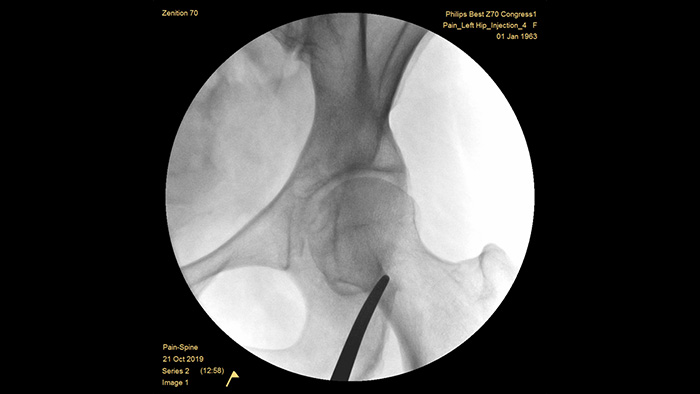

Philips se ha forjado una reputación de excelencia en la obtención de imágenes y la eficiencia de las dosis a lo largo de medio siglo de experiencia en el desarrollo de sistemas de arco en C móviles para el entorno quirúrgico. Nuestras soluciones de cirugía móvil Zenition se basan en un enfoque integral de la gestión de dosis. Proporcionan una calidad de imagen clínicamente relevante durante los procedimientos intervencionistas para aplicaciones de gestión del dolor, al tiempo que gestionan, de forma eficiente, la exposición a la radiación de los pacientes y el personal médico.

La profundidad óptima del arco en C totalmente contrabalanceado proporciona un amplio espacio para posicionarse alrededor de los pacientes obesos, y obtener imágenes de la columna lumbar y la cadera. Admite la colocación sobre la mesa, incluso para las mesas que tienen una base grande.